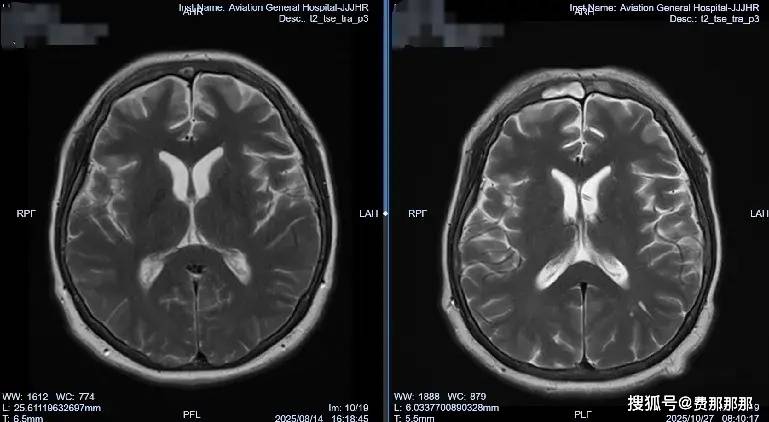

肖庆主任决定采取分阶段治疗策略:首先在2025年8月13日进行“腰大池置管引流”,建立初步引流通道;随后在8月21日实施“脑室腹壁外引流术”,建立持续引流通道。“精准的脑脊液管理是真菌性颅内感染治疗的关键。”肖主任强调,“我们不仅要控制感染,更要通过精细的引流调节,维持正常的颅内环境,为大脑恢复创造最佳条件。”

治疗过程中的每一个环节都体现了肖庆团队对细节的精准把控。在持续引流和抗真菌治疗双管齐下后,李女士的脑脊液化验指标开始逐渐好转。

肖庆主任表示,这个病例的成功得益于“个体化的脑脊液管理策略”与“精准的抗真菌治疗”的完美结合。“真菌性颅内感染治疗的最大挑战在于,它容易导致脑室系统粘连,进而形成脑积水。而通过精准的脑脊液外引流管理,我们不仅控制了颅内压力,还直接改善了药物分布,防止了并发症的发生。”